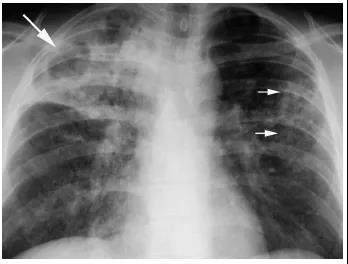

根据国家《学校结核病防控工作规范(2017版)》要求学校按有关规定将结核病检查项目作为新生入学体检和教职员工常规体检的必查项目,无论是初中、高中还是大学的入学新生,在入学一个月内要做胸部X光片检查,以期早期发现肺结核患者,避免传染给其他的同学。

肺结核的X线影像表现图片来源:医脉通